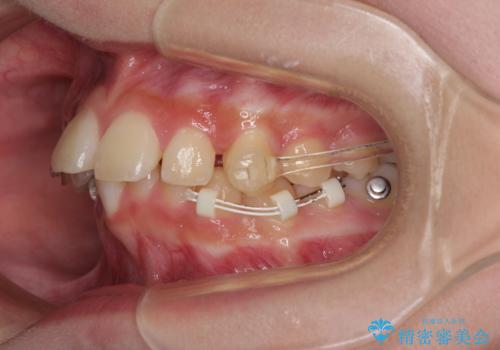

インビザライン単体で対応ることも検討できますが、達成する可能性が低いため、カリエールディスタライザーという補助装置を併用して、より確実性を上げることとしました。

奥歯の咬み合わせと深い咬み合わせを改善した後、インビザラインで歯列を整えることとしました。